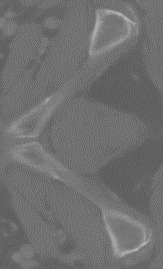

Figure 4: (a) The axial slice generated from Isagsubscript𝐼𝑠𝑎𝑔I_{sag}. (b) The axial slice generated from Icorsubscript𝐼𝑐𝑜𝑟I_{cor}. Some details are better resolved by (a) and others by (b). Both of them exhibit directional artifact due to a lack of constraints in the (x,y) plane. This is resolved through RFN in (d), which refines their average Iavgsubscript𝐼𝑎𝑣𝑔I_{avg}, as shown in (c)

where Igtx=Ix(y,z)subscriptsuperscript𝐼𝑥𝑔𝑡superscript𝐼𝑥𝑦𝑧I^{x}_{gt}=I^{x}(y,z) and Igty=Iy(x,z)subscriptsuperscript𝐼𝑦𝑔𝑡superscript𝐼𝑦𝑥𝑧I^{y}_{gt}=I^{y}(x,z) in the densely-sampled volume I𝐼I. From the axial perspective, Isag(x,y,z)subscript𝐼𝑠𝑎𝑔𝑥𝑦𝑧I_{sag}(x,y,z) and Icor(x,y,z)subscript𝐼𝑐𝑜𝑟𝑥𝑦𝑧I_{cor}(x,y,z) provide line-by-line estimations for the missing axial slices. However, since no constraint is enforced on the estimated axial slices, inconsistent interpolations lead to noticeable artifacts, as shown in Fig. 4. We resolve this problem in the RFN stage of the proposed pipeline.

RFN further improves the quality of slice interpolation by learning the structural variations within individual slices. As shown in Fig. 5, we first take the axial slices of the sagitally and coronally super-resovled volumes Isag(x,y,z)subscript𝐼𝑠𝑎𝑔𝑥𝑦𝑧I_{sag}(x,y,z) and Icor(x,y,z)subscript𝐼𝑐𝑜𝑟𝑥𝑦𝑧I_{cor}(x,y,z) to obtain Isagz(x,y)superscriptsubscript𝐼𝑠𝑎𝑔𝑧𝑥𝑦I_{sag}^{z}(x,y) and Icorz(x,y)superscriptsubscript𝐼𝑐𝑜𝑟𝑧𝑥𝑦I_{cor}^{z}(x,y), respectively. As each pixel from Isagz(x,y)superscriptsubscript𝐼𝑠𝑎𝑔𝑧𝑥𝑦I_{sag}^{z}(x,y) and Icorz(x,y)superscriptsubscript𝐼𝑐𝑜𝑟𝑧𝑥𝑦I_{cor}^{z}(x,y) represents the best estimate from the sagittal and coronal directions, an average of the slices Iavgz(x,y)superscriptsubscript𝐼𝑎𝑣𝑔𝑧𝑥𝑦I_{avg}^{z}(x,y) can reduce some of the directional artifacts. We then apply residual learning, which has been proven to be effective in many image-to-image tasks [17, 15, 27], with fusion network ϕsubscriptitalic-ϕ\mathcal{F_{\phi}}: